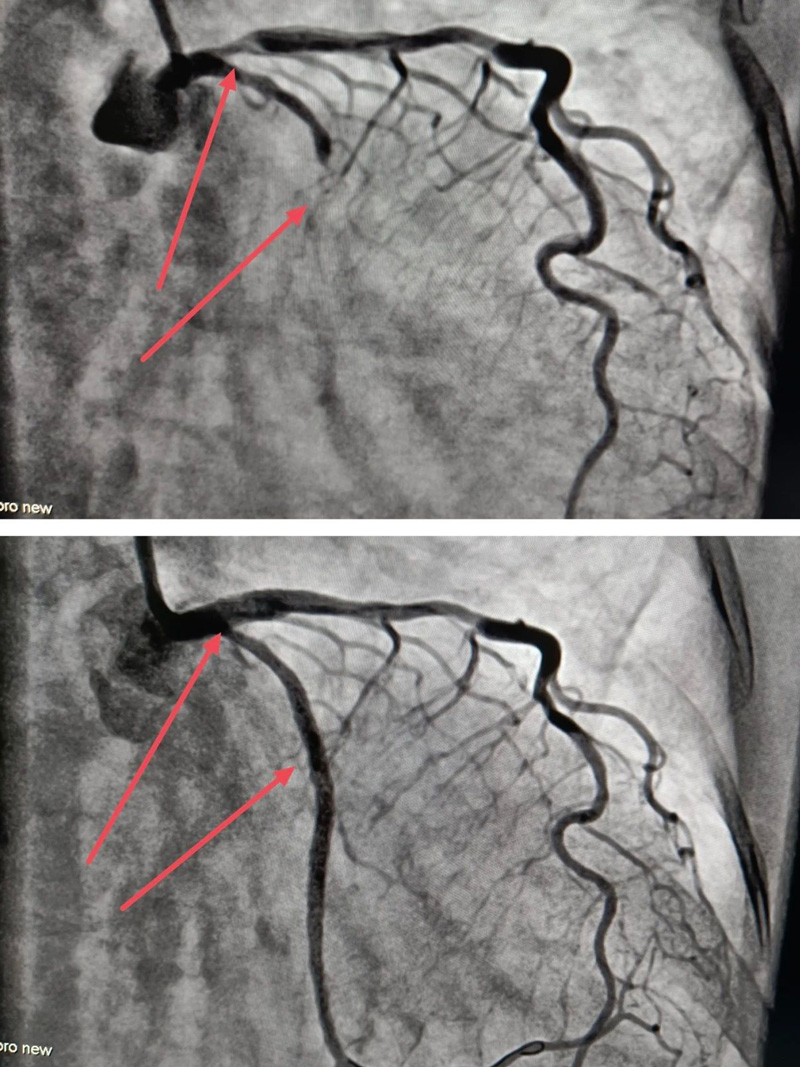

来凤县人民医院心血管内科首次开展IVUS(血管内超声)指导下冠脉复杂介入治疗,并顺利完成2例IVUS指导下精准支架植入术。

3月15日,来凤县人民医院副院长张承中、心血管内科主任朱兴彪及介入团队其他成员,全面评估患者病情后,决定在IVUS的指导下,精准植入支架——球囊扩张、IVUS检查、支架植入、复查IVUS,整个手术不到两小时,复查IVUS和造影结果非常满意,患者无任何不适。

来凤县人民医院心血管内科开展IVUS指导下的PCI治疗,由于该技术难度较大,对术者水平要求高,这不仅标志着来凤县人民医院心血管内科介入团队在处理冠脉复杂病变技术上又有了新的突破,同时这项技术的开展,也为冠心病患者提供了更规范的诊断流程和更精确的治疗手段。

IVUS(血管内超声)是通过导管技术将微型超声探头送入血管腔内,显示血管横截面图像,从而提供在体血管腔内影像的一种技术。与冠脉造影只能对血管内血流情况进行成像,且容易受造影角度的影响,无法对血管壁上的斑块发展情况进行判断相比,IVUS能够精确测定管腔、血管直径以及判断病变严重程度及性质,在提高对冠状动脉病变的认识和指导介入治疗方面起了非常重要的作用。